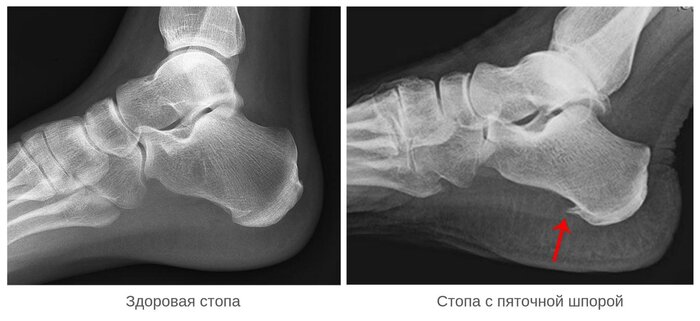

В прошлом посте я поднимал тему энтезопатий. Еще раз повторю кратко, энтезопатия - это систематическая микротравматизация волокон сухожилия или связки, которые вызывают воспаление и болевой синдром, чаще всего в местах их прикрепления (где слабо, там и рвется). И основная проблема у людей с дегенеративным заболеванием стоп - это плантарный фасциит, или как называют его в простонародье - пяточная шпора. Довольно часто я встречают мифы связанные с этой патологией и люди постоянно путают причину со следствием. Эта самая "пяточная шпора" является следствием адаптационного механизма к систематической микротравматизации подошвенного апоневроза (плантарной фасции) в виде оссификации места прикрепления к бугристости пяточной кости. Звучит страшно, но дальше я объясню.

Итак. Болевой синдром плантарного фасциита связан с образованием "порочного круга" и проявляется неудовлетворительнойрегенеративной активностью для той самой микротравматизации. День Х, по какой-то из причин произошла травматизация подошвенного апоневроза. Вы можете даже не почувствовать дискомфорта, а можете просто почувствовать ту самую "усталость" в ногах. Позже, ночью, вы ложитесь спать. В положении лежа стопа расслабляется и подошвенная фасция укорачивается, ввиду отсутствия воздействующей на нее растягивающей нагрузки, попутно организм пытается регенерировать ту самую микротравму. Биохимические процессы текут в организме достаточно быстро и интенсивно, однако иногда времени полноценного сна не хватает для сращения травмированной связки и она заживает частично. Приходит утро, и по привычке, без какого-либо опасения, вы встаете на эту стопу с полной нагрузкой. Плантарная фасция не справляется с нагрузкой и рвется до исходного состояния, а может еще больше. Следующие сутки ситуация повторяется и вы вместе со своей стопой попадаете в этот "порочный круг". Данные циклы происходят и при длительном нахождении в положении сидя, там тоже стопа расслабляется, а регенерация происходит в нашем организме постоянно. Кстати, именно поэтому при плантарном фасциите люди испытывают "стартовые" боли по утрам и после длительного нахождения в покое. Изо дня в день, организм пытается скомпенсировать данную проблему, единственный разумный вариант для него - это отложение минералов в связку для того, чтобы повысить ее жесткость. А эту минерализацию связки мы и видим на рентгене и называем ее "пяточной шпорой". Нет она не давит вам в кожу, не создают колющие боли в пятке - это следствие систематической перегрузки подошвенного апоневроза, это он сам и есть. Почему-то многие думают (в том числе и доктора), что это процесс может происходить только в месте прикрепления связки к пятке. Да, чаще всего там все и происходит, так как там наиболее слабое место. Но встречается и плантарный фасциит, при котором симптомы локализуются в переднем отделе стопы.